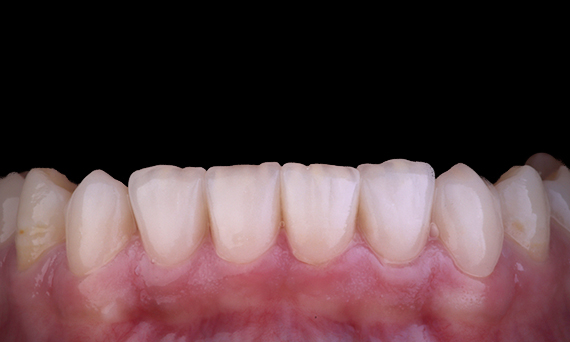

A menudo, los pacientes desconocen las grietas o caries de sus dientes. Solo cuando un diente duele o se rompe, la mayoría de los pacientes se dan cuenta de la necesidad de revisarse los dientes. En general, podemos evitar cosas como el agrietamiento de dientes, en función de la presencia de grietas existentes, oclusión pesada o antecedentes de pérdida de dientes anterior debido a una grieta. En este caso, el paciente tenía un diente premolar superior agrietado asintomático que se observó durante un chequeo dental de rutina. Se le mostró al paciente la fotografía del diente y se le informó la situación, con la recomendación de realizarse una restauración. Sin embargo, el paciente rechazó cualquier tratamiento ya que no estaba experimentando ningún síntoma del diente. Seis meses después, el diente se agrietó y ahora el paciente ya no podía dilatar el tratamiento. El diente se restauró con CEREC con una corona/incrustaciones dentales onlay de resina cerámica híbrida en una visita.

Dr. Sahil Soni, Queensland, Australia